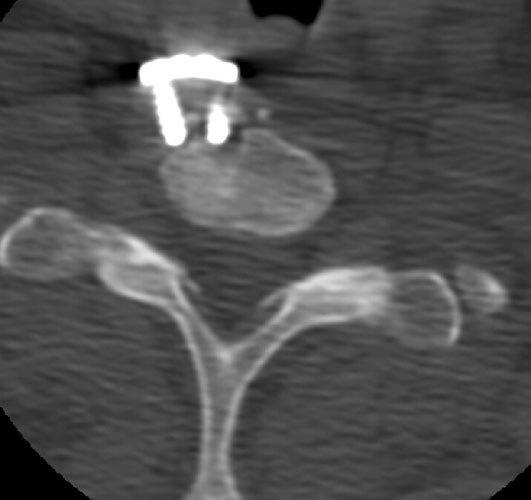

This axial CT taken at the same time shows to

better advantage how the distal screws are fully out of the ventral cortex of C7

on the right hand distal screw and only 1 thread of the left hand distal screw

remains in the bone itself. The fixation plate is also 1cm ventral to the body

of C7 at this level. |